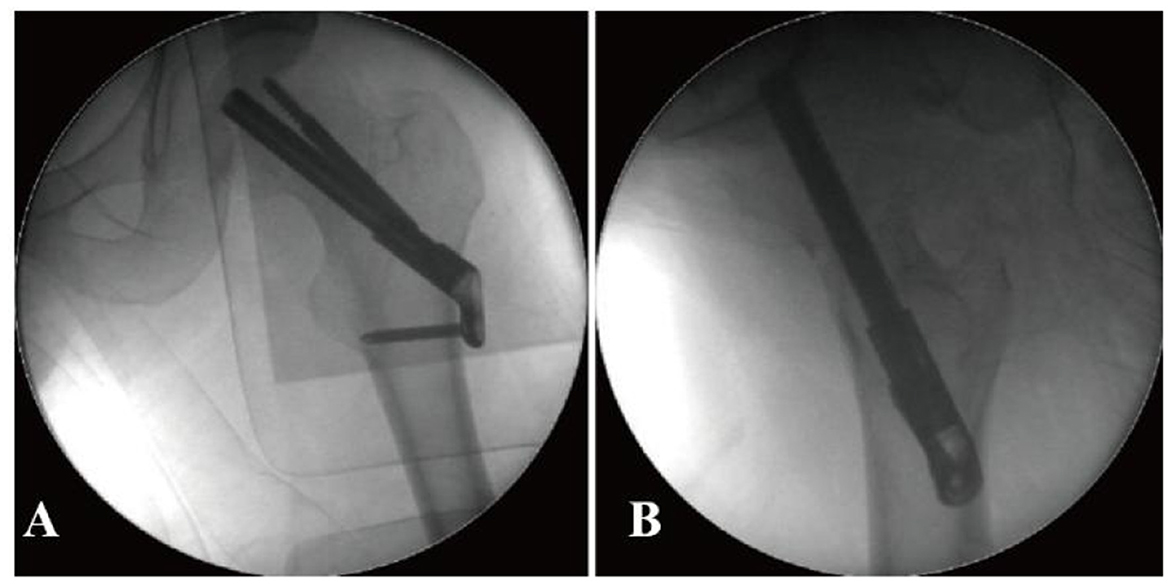

A 5 cm skin incision was made along the proximal thigh at the level of the lateral malleolus, where the longitudinal axis of the femoral stem intersects. A 130° angular guide was used for the insertion of a power bar, positioned in the middle and lower part of the femoral neck in the orthopedic position, or slightly posterior to the femoral neck in the lateral position. The length of the power bar was measured, an opening was created, and the FNS (Johnson & Johnson) power bar was inserted, ensuring the tip of the bar was 5 mm from the subchondral bone of the femoral head. The locking head screw and the anti-retroviral screw were then inserted sequentially. The FNS was positioned satisfactorily on the C-arm X-ray, the two anti-retroviral Kirschner pins were removed, and the wound was irrigated and closed in layers, with a sterile dressing applied (Figure 2).

Prior to the final implantation of the FNS, a pre-compression technique was employed. This involved adjusting the sliding distance of the implant before its insertion and limiting the sliding distance to within 5 mm. The specific surgical procedure is shown in Figure 3.

Radiographic and procedural details of FNS implantation in a 41-year-old male with a femoral neck fracture. (A, B) Anteroposterior and lateral views show the position of the implant. The tip of the FNS dynamic bolt was placed 5 mm from the femoral subchondral bone, followed by sequential insertion of the locking head screw and the anti-rotation screw. Due to impaction of the posterior cortex, the sliding distance of the FNS was preoperatively adjusted and limited to within 5 mm before final implantation to prevent excessive femoral neck shortening.